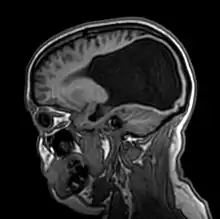

Colpocephaly is characterized by disproportionately large occipital horns of the lateral ventricles (also frontal and temporal ventricles in some cases). MRI and CT scans of patients demonstrate abnormally thick gray matter with thin poorly myelinated white matter. This happens as a result of partial or complete absence of the corpus callosum. Corpus callosum is the band of white matter connecting the two cerebral hemispheres. The corpus callosum plays an extremely important role in interhemispheric communication, thus lack of or absence of these neural fibers results in a number of disabilities.[12]

After birth, MR imaging can be done to look for cephalic abnormalities. This is the most commonly used method for diagnosing colpocephaly. Physicians look for abnormally large occipital horns of the lateral ventricles and diminished thickness of white matter.[12] Spinal tapping is not a preferred method for diagnosis because newborn babies with colpocephaly or hydrocephaly have open fontanelles which makes it difficult to collect CSF. Also, colpocephaly is not associated with increased pressure.[13]